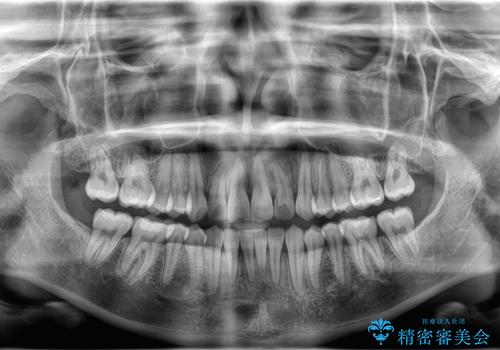

治療計画をしっかり立て、歯の移動量や力のコントロールを最適化することで、約1年という短期間で矯正治療を終了することができました。

治療後は歯並び・かみ合わせともに大きく改善し、患者様にも大変ご満足いただけました。